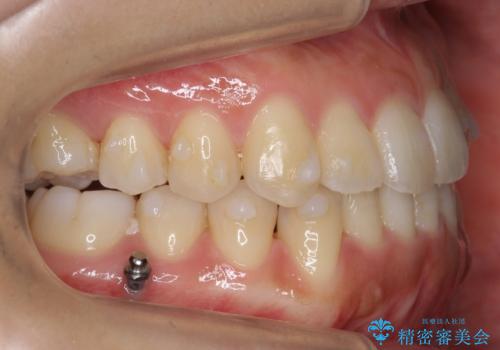

矯正用ミニスクリューを用いて治療しています。

奥歯のかみ合わせの前後的なずれをそのままにして治療すると、前歯が突き上げるような状態になってしまいます。

ただその場で並べるのではなく、症状によっては奥歯を後ろに下げる必要があります。